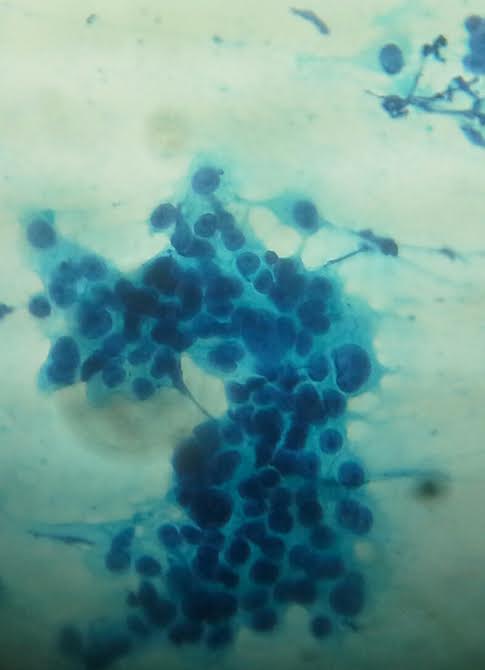

Cytology description

- Can use cellular pleomorphism, nuclear size, nuclear margin, nucleoli, lack of naked nuclei, cellular dyscohesion and mitoses in addition to necrosis to assess cytologic tumor grade, which correlates with histologic grade (Diagn Cytopathol 2003;29:185)

Cytology images